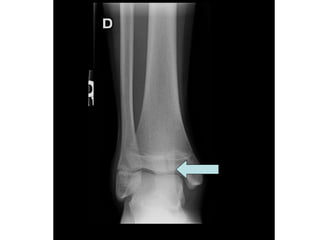

Diagnostic ?

A. Salter 1

B. Entorse cheville

C. Entorse haute

D. Salter 3

E. Avulsion

Fracture de Tillaux

• Salter 3

• Fracture de la portion latéral de

l’épiphyse du tibia distal

• La portion médiane de la physe du tibia

ayant déjà commencé à se fusionner

Conduite

• Atelle postérieure

• Référé 24 heures

• Aviser résident de garde ortho